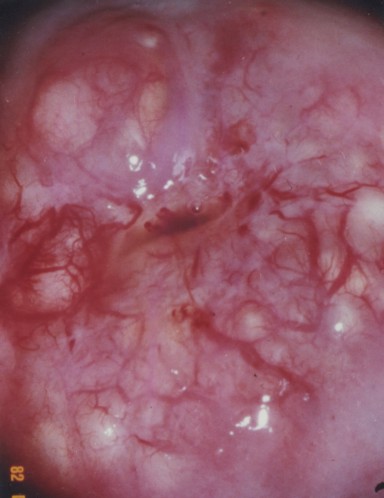

CISTO DE NABOTH ( NO COLO UTERINO )

As glândulas da superfície interna do canal do colo uterino que as vezes se exteriorização podem ficar cheias de secreção devido ao bloqueio no ducto ou passagem na glândula. Conforme as secreções se acumulam, um nódulo arredondado e liso pode formar-se sob a superfície do colo do útero vindo a tornar-se grande o suficiente para ser visto ou sentido durante um exame ginecológico. Cada cisto caracteriza-se como uma elevação pequena, de cor branca, hipervascularizada como uma pústula. Os cistos podem ocorrer isoladamente ou em grupos e, embora não sejam uma ameaça à saúde, são indicativos de uma infecção passada ou recente, cauterizações de feridas na colo uterino ou de irritação no colo do útero. Os cistos são mais comuns em mulheres em idade reprodutiva, especialmente naquelas que já tiveram filhos.

Embora nenhum sintoma que indique a sua ocorrência possa ser observado, ao exame ginecológico de rotina revela-se como um nódulo arredondado, pequeno e liso (isolado ou grupos) na superfície do colo uterino. Em raras ocasiões, um exame colposcópico faz-se necessário para distinguir os cistos de Naboth de outros tipos de lesões cervicais. Não existe método de prevenção conhecido.